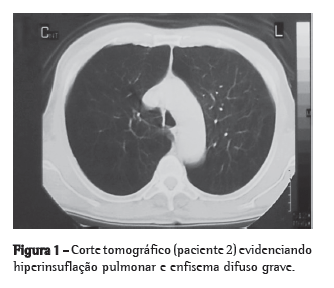

Em 2004, procurou-se localizar todos os participantes da coorte de 1993, atingindo-se um percentual de 87,5% (4.452 adolescentes). Das 981 crianças da subamostra aos 4 anos, foram localizados e entrevistados, em 2004, um total de 897 adolescentes (Figura 1).